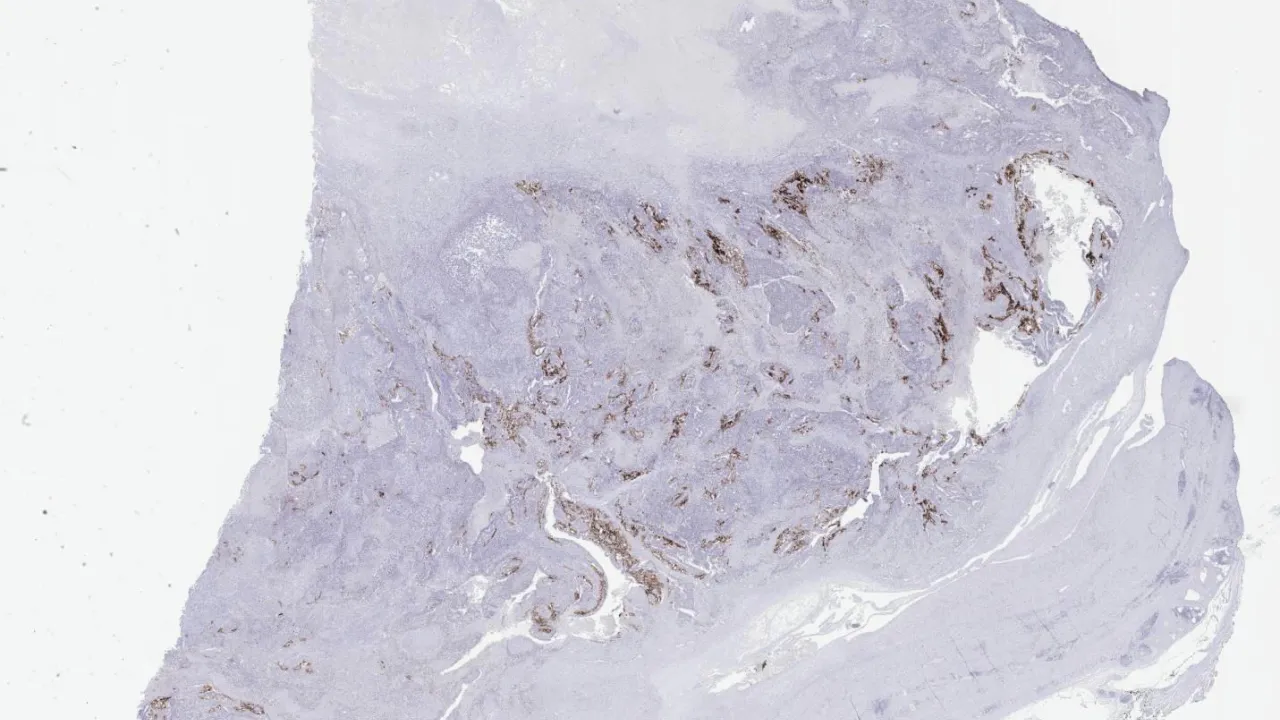

Testis, Mixed germ cell tumour, B-HCG stain

Testis, Mixed germ cell tumour, CD30 stain

Testis, Mixed germ cell tumour, Glypican stain

Testis, Mixed germ cell tumour, H&E stain